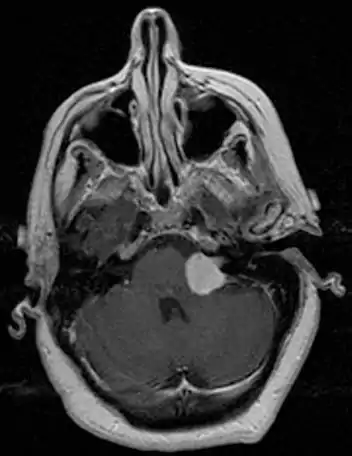

MRI scan is the imaging of choice because it can more accurately differentiate the mass from other tumors such as meningioma, facial nerve schwannoma, epidermoid cyst, arachnoid cyst, aneurysm, and brain metastasis. MRI scan also helps in surgical planning and follow-up of the tumor after surgery.[19] VC is usually isointense on T1 weighted images, hyperintense on T2 weighted images, and enhances after given gadolinium contrast.[20] The use of MRI however should be used appropriately as patients with unilateral tinnitus alone

There have been cases of tumors that were actually asymptomatic until very large and at a critical stage. Tumor growth rates are highly variable: some small VSs (perhaps 50%) do not grow at all; some few grow for a time and then shrink; some appear dormant but suddenly grow rapidly. In general, although studies differ, VSs that grow are slow-growing at an average rate of 1.2 to 1.9 mm per year. IAC tumors that grow beyond 1.5 cm in diameter expand into the relatively empty space of the cerebellopontine angle, taking on the characteristic 'ice-cream-cone' appearance seen on MRIs. As 'space-occupying-lesions,' the tumors can reach 3 to 4 cm or more in size and infringe on the facial nerve (facial expression) and trigeminal nerve (facial sensation). Advanced hearing loss and spells of true vertigo may occur. Very large tumors are life-threatening when they press on the cerebellum or cause brainstem compression. Late symptoms of very large VS include headache, nausea, vomiting, sleepiness, mental confusion and eventually coma.[3][4]